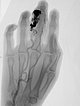

Fluoroskopische Darstellung des Cast nach erfolgreicher Nidusembolisation der AVM. Zur besseren Orientierung für die Operationsplanung erfolgt diese Darstellung auch noch einmal ohne Subtraktion mit sichtbaren Knochen.